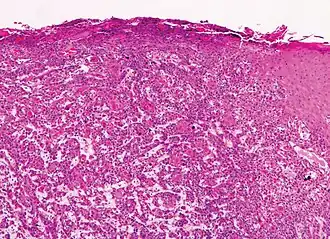

Invasive disease

In invasive cSCC, tumor cells infiltrate through the basement membrane. The infiltrate can be somewhat difficult to detect in the early stages of invasion: however, additional indicators such as full-thickness epidermal atypia and the involvement of hair follicles can be used to facilitate the diagnosis. Later stages of invasion are characterized by the formation of nests of atypical tumor cells in the dermis, often with a corresponding inflammatory infiltrate.[12]

-

Gross slice of squamous-cell carcinoma of the skin -

Superficially invasive cutaneous squamous-cell carcinoma. These lesions often do not show the marked pleomorphism and atypical nuclei of cSCC in situ, but manifest early keratinocyte invasion of the dermis.[12] -

High magnification demonstrates the pleomorphism of the invading keratinocytes[12] -

Invasive nests with characteristic large celled centers. Ulceration (at left) is common in invasive cSCC.